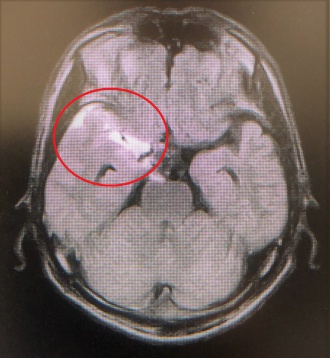

2020年01月18日(土) くも膜下出血の患者さん 当番医の時に頭痛で受診したくも膜下出血の患者さんの報告書が、紹介先の病院から届きました。 脳動脈瘤の破裂が原因で、血管内手術を行って治療したようです。経過は順調であり安堵しました。 この患者さんは、急な頭痛で近くの内科で処方された痛み止めが効かなかったようです。 このように、急に起きた頭痛、痛み止めが効かない頭痛は要注意です。 左写真は頭部MRI検査で、赤丸がくも膜下出血の部位です。 右写真は脳血管造影検査で、赤丸が脳動脈瘤です。